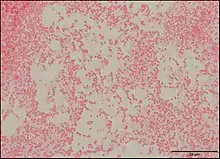

Pseudescherichia vulneris is a Gram-negative bacterial species. P. vulneris is a fermentative, oxidase-negative, motile rod, which holds characteristics of the family Enterobacteraceae. This bacterium can colonize in the respiratory tract, genital tract, stool, and urinary tract. However, P. vulneris is most often associated with wounds and has been known to colonize open wounds of both humans and animals. This association gave the bacterium its species name, vulneris, which is Latin for wound. It has also been infrequently reported in cases of meningitis. It was identified as Escherichia vulneris in 1982 with a 2017 genomic analysis of its original genus resulting in the creation of its new genus Pseudescherichia.[1][2]

P. vulneris has a rod-like (bacilli) shape, and it achieves motility using peritrichous flagella (covering the whole body of the bacteria). P. vulneris is facultatively anaerobic, and is not spore-forming. Optimal growth occurs at 35-37°C, and it can colonize on a simple nutrient medium. Colonies are generally smooth and low convex with shiny surfaces.[3]